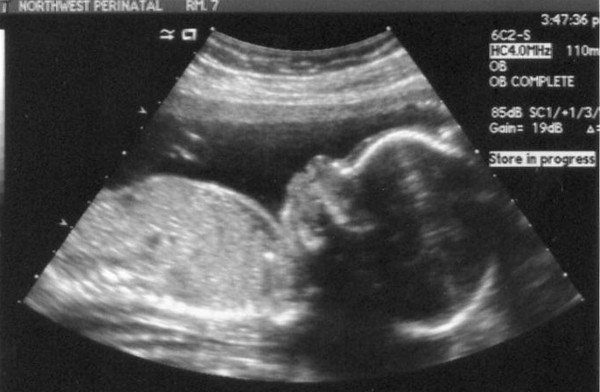

We had yet another ultrasound today. Things are looking good! Here are a few pictures to share.

This was our favorite picture from today - a decent view of Junior's face. Doesn't it kind of look like he is grinning?

Here is a profile shot with the mouth open. The sonographer said that the little 'bubble' next to his mouth is actually the umbilical cord. The other floating things there is actually a hand with the middle out of view.